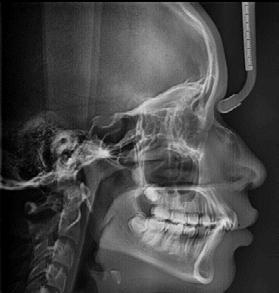

En la radiografía lateral de cráneo se observa un crecimiento hiperdivergente y la clase II esquelética con un Witts de 2 mm (Figura 7). En panorámica, 31 dientes permanentes presentes con terceros molares impactados y ausencia de OD 48 (Figura 8).

En la radiografía lateral de cráneo se ve la clase II esquelética, con crecimiento hiperdivergente, hiperplasia sagital maxilar y proinclinación del incisivo mandibular (Figura 6).